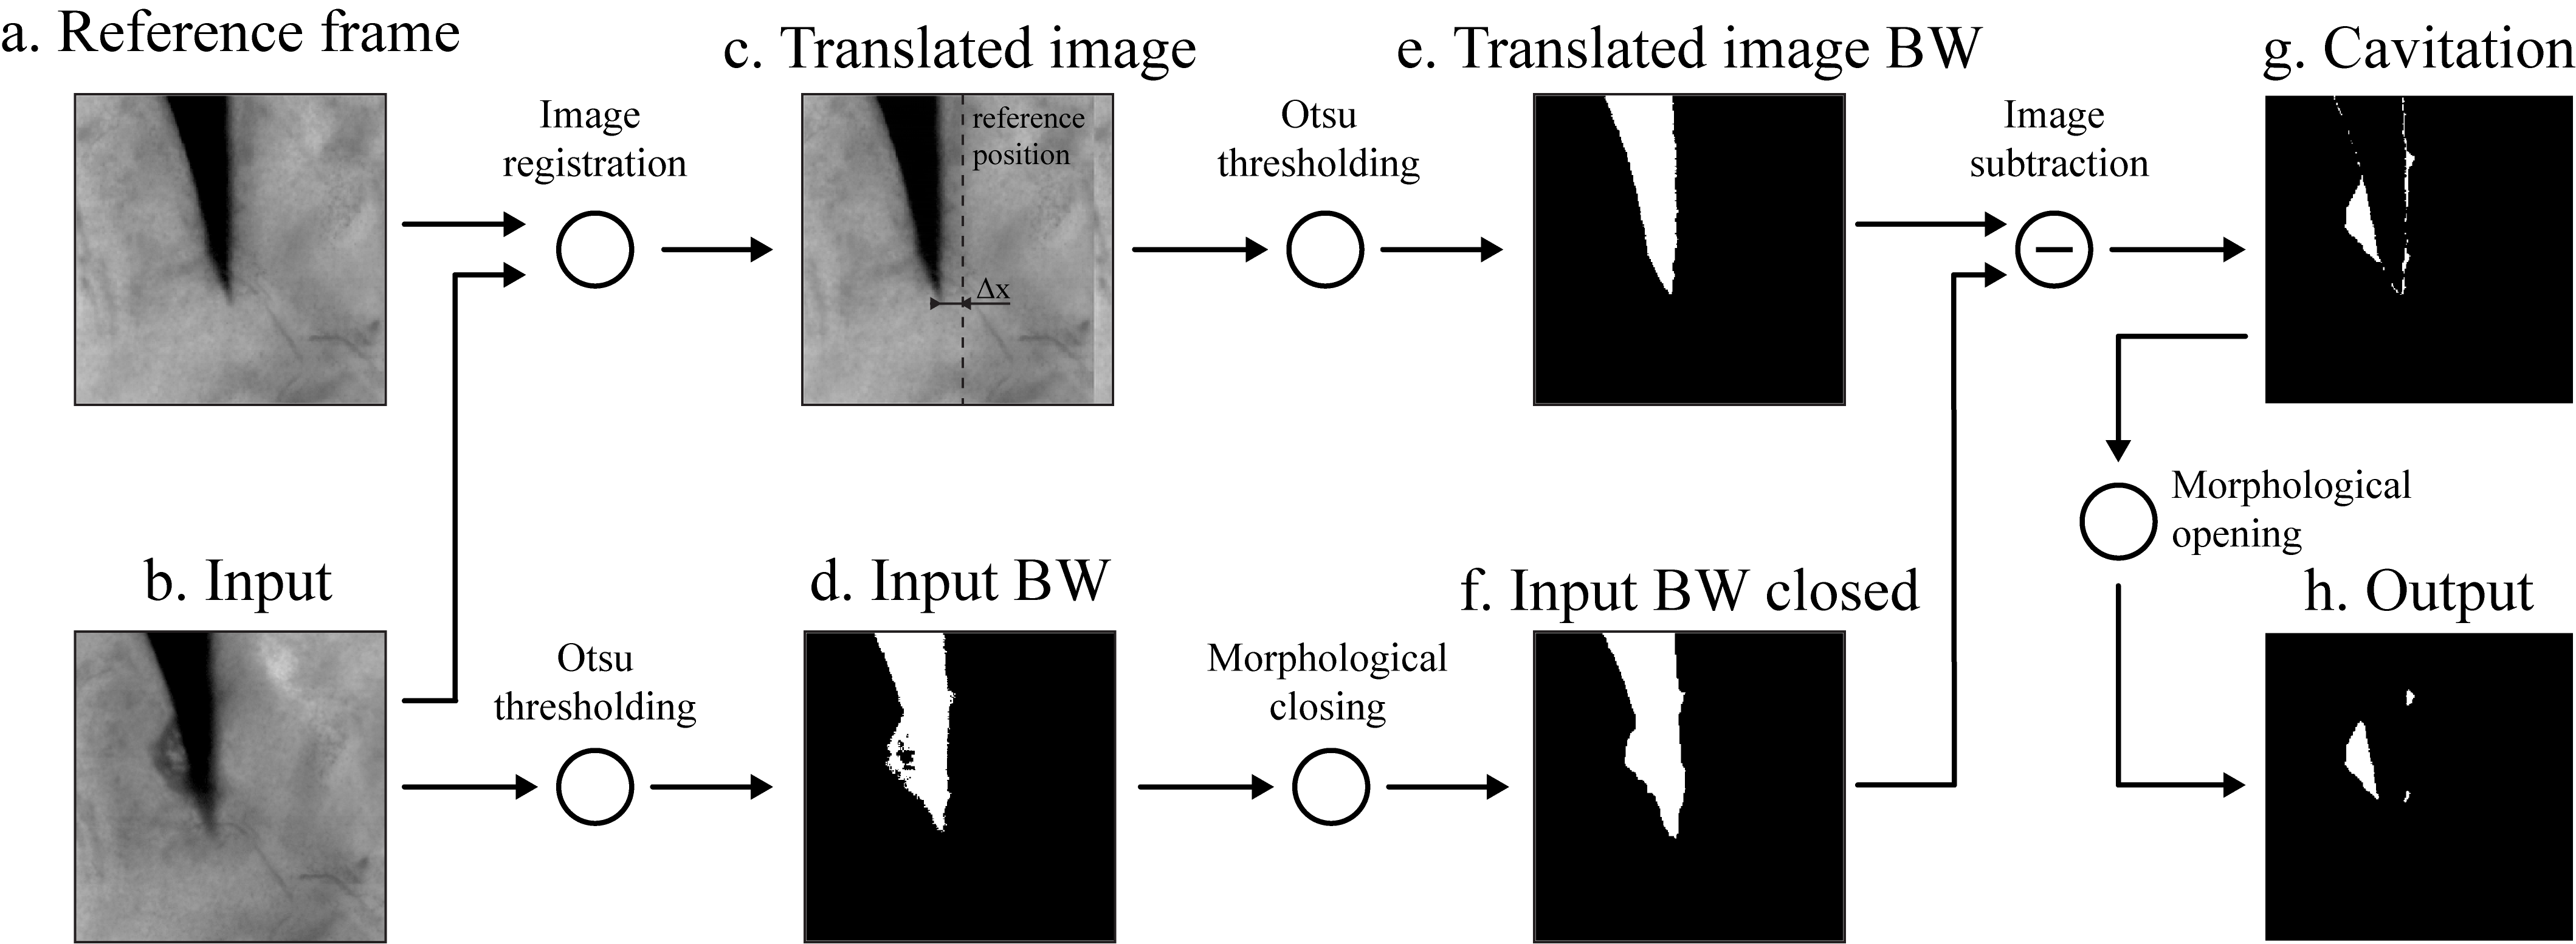

The HS frames were analysed in MATLAB (R2020b) Mathworks2016 to quantify the projected area of cavitation and the needle displacement using a similar method presented in our recent publicationPerra2021 . A cross-correlation based image registration was performed along the x-axis between the reference frame I1subscript𝐼1I_{1} and the the i-th frame Iisubscript𝐼𝑖I_{i}, in order to estimate the needle displacement ΔxiΔsubscript𝑥𝑖\Delta x_{i} from its reference position. The image I1subscript𝐼1I_{1} was then rigidly translated by ΔxiΔsubscript𝑥𝑖\Delta x_{i} and thresholded with the Otsu methodOtsu1996 , while an Otsu thresholding followed by a morphological closing operation (circular structuring element, diameter = 7 pixels) was applied to the image Iisubscript𝐼𝑖I_{i}. The segmented image Icav,isubscript𝐼𝑐𝑎𝑣𝑖I_{cav,i} showing only the cavitation activity is obtained by subtracting the binarized reference image Ibw,1subscript𝐼𝑏𝑤1I_{bw,1} from the closed image Ibw,isubscript𝐼𝑏𝑤𝑖I_{bw,i}. Since the needle shape in Ibw,1subscript𝐼𝑏𝑤1I_{bw,1} does not perfectly match the one in Ibw,isubscript𝐼𝑏𝑤𝑖I_{bw,i}, a final morphological opening operation (circular structuring element, diameter = 3 pixels) was applied to the output Icav,isubscript𝐼𝑐𝑎𝑣𝑖I_{cav,i} in order remove any pixels that may have remained after the subtraction operation and that are not representative of the cavitation activity.

Figure 2: General description of the segmentation process of the HS video frames. A cross-correlation based image registration is applied along the x-axis between (a) the reference frame and the (b) i-th frame, in order to estimate the displacement ΔxiΔsubscript𝑥𝑖\Delta x_{i} of the needle tip from its reference position. (c) The reference frame is then translated horizontally by ΔxiΔsubscript𝑥𝑖\Delta x_{i}, while (d) the input frame is thresholded with the Otsu method. (e) The binary image showing the translated reference frame is subtracted to (f) the thresholded input frame, which was previously closed with a morphological closing operation. (g) The result of the subtraction is finally filtered with a morphological opening operation, in order to produce (h) the binary mask for the cavitation activity.